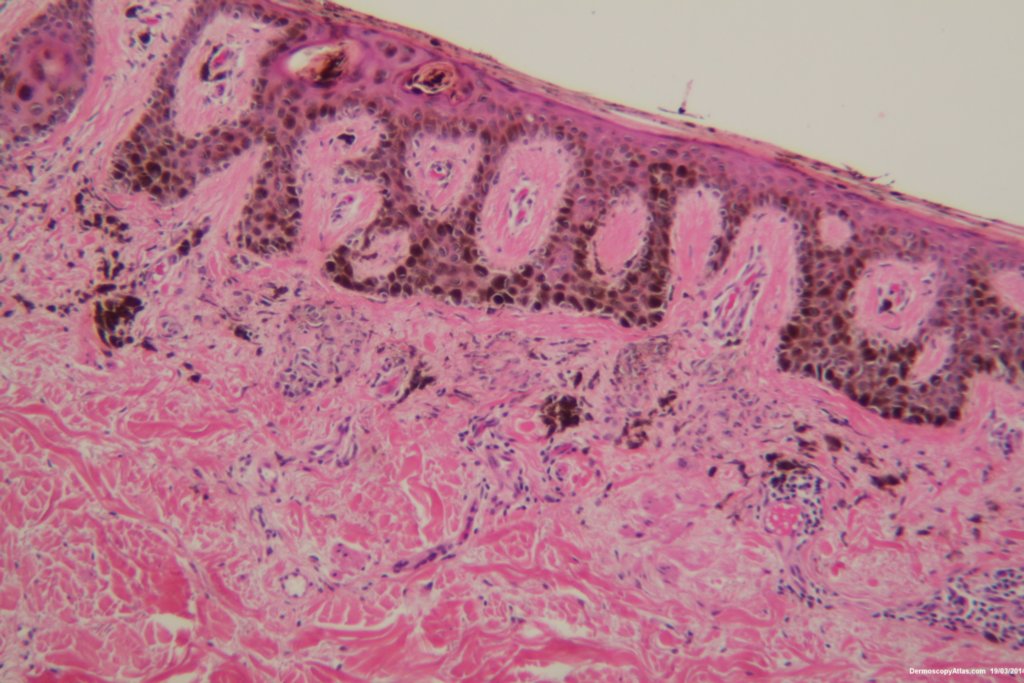

Diagnosis: Dysplastic Junctional Lentiginous Nevus

An elderly male asked about the pigmented lesion on his lower back. The dermatoscopy showed internal lines and dark clods with a central dark structureless area. Histology showed a dysplastic junctional lentiginous nevus.